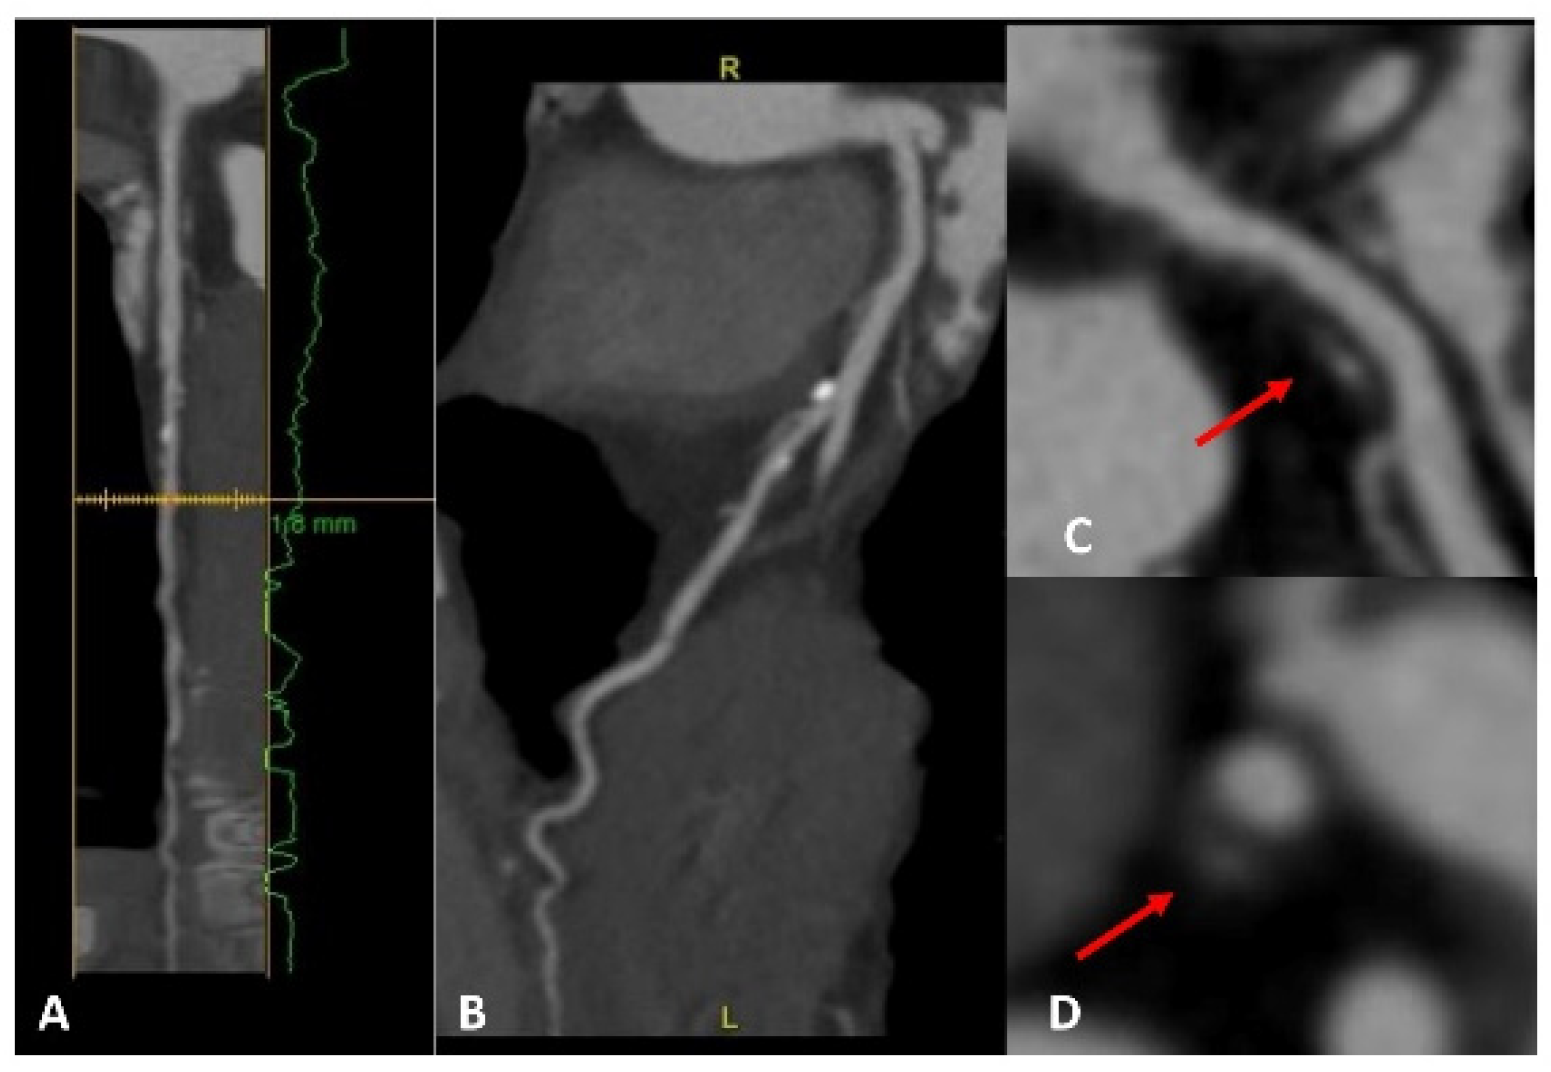

5.2. Advances in CAD Assessment Using CCTA